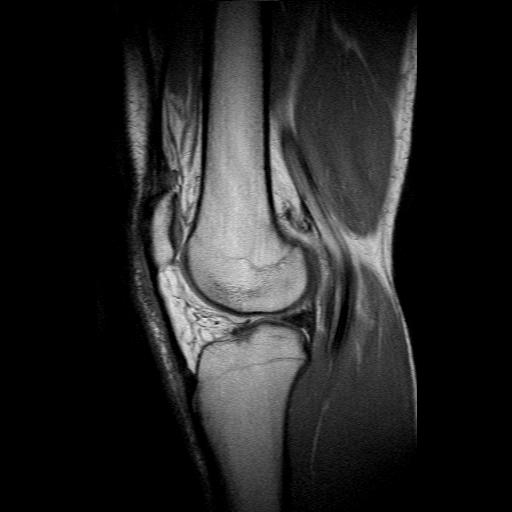

-les liquides: le liquide céphalo rachidien sur une coupe du cerveau (=liquide qui baigne le cerveau, donc en gros c'est la couleur du cerveau quoi), le liquide synovial dans une articulation...

-la corticale des os: c'est un milieu complètement exempt d'eau. Il sera donc en hyposignal dans les pondération rho